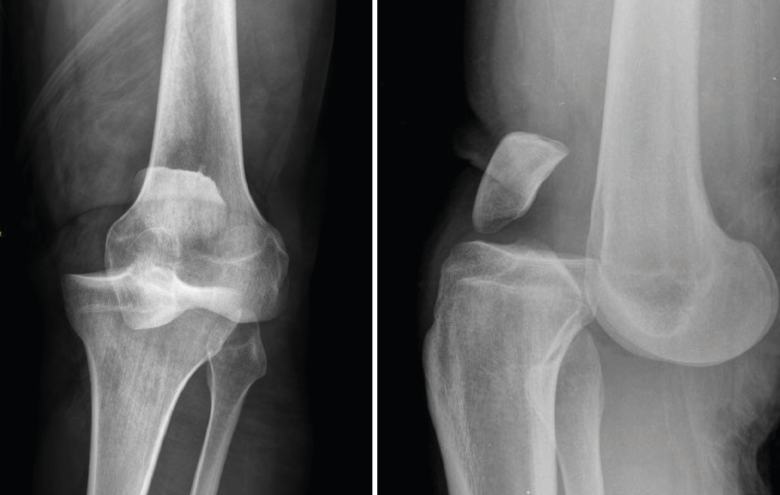

1.2. Luxación femorotibial

La luxación traumática de rodilla es una entidad poco frecuente, que representa menos del 0,5% del total de las luxaciones articulares(3).

Requiere un tratamiento precoz, ya que una de sus complicaciones más graves es la lesión de la arteria poplítea, para cuyo diagnóstico se recomienda realizar un estudio de angio-TAC (Figura 4).

Figura 4. Radiografías anteroposterior y lateral de rodilla: luxación anterior de tibia y peroné.